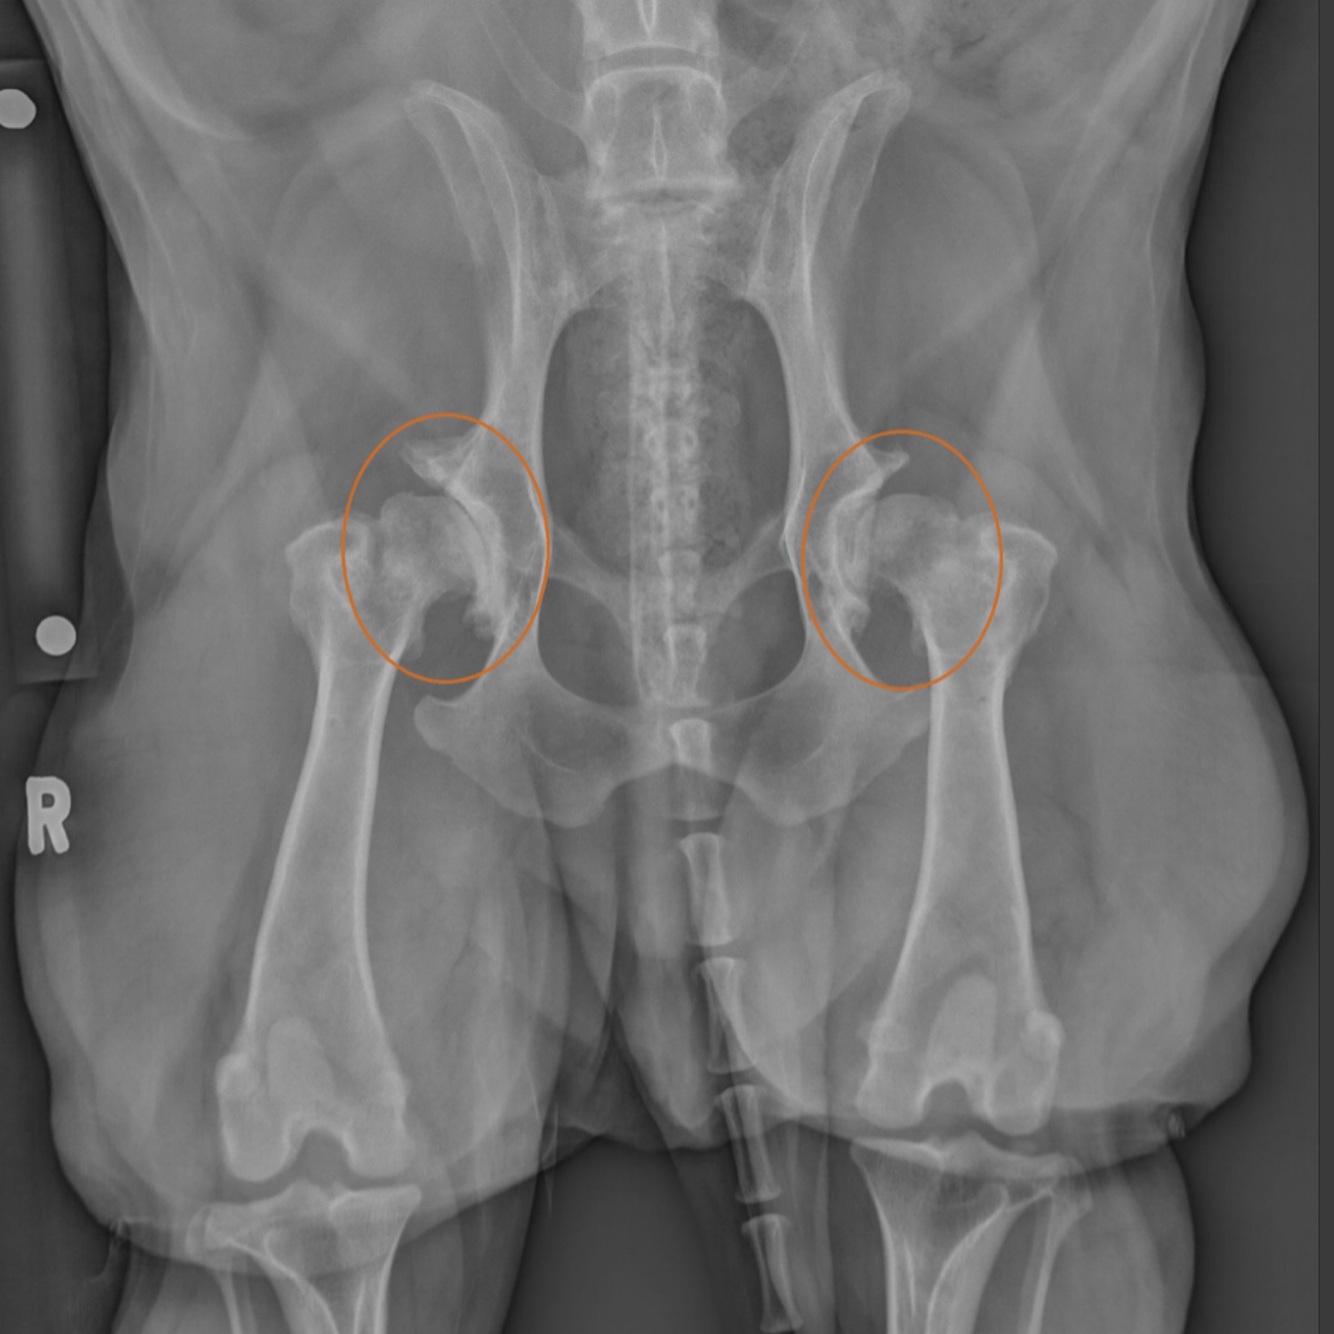

A 10 year old female spayed Dachshund presents for further evaluation of progressive lameness in the hind.

The owner notes that she has begun intermittently scuffing her hind limbs, has somewhat of a weak or drunken gait in the hind as she walks, and is having trouble rising. Given the answer choices below, what is the best treatment?

Answer: Dorsal laminectomy

This patient’s clinical signs are consistent with neurological deficits. Although you do not have all of the information necessary to reach a definitive diagnosis, you should have been able to deduce that this patient probably needs a dorsal laminectomy to relieve disc compression.

In order to definitively diagnose the condition you would want to proceed with a complete exam, basic bloodwork, and a CT or MRI of the lumbosacral region. Although this patient does exhibit evidence of hip dysplasia radiographically, the clinical signs are not characteristic of a dog with pain secondary to hip dysplasia. There is no indication of osteomyelitis on these radiographs and the clinical signs are not necessarily suggestive of osteomyelitis.

It is important not to skip ahead to image interpretation without carefully reading the question. Doing so in this case would likely lead you to select the incorrect answer.

Radiographs provided by Adrien Hesperian, DVM, MS, DACVR and University of Tennessee College of Veterinary Medicine